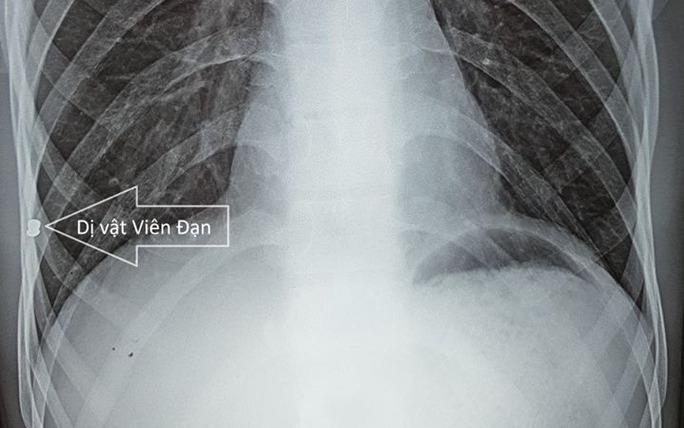

Một nam thanh niên bị đạn bắn vào người từ nhỏ và suốt hơn 20 năm phải sống trong nơm nớp lo sợ do không lấy đạn ra ngoài.